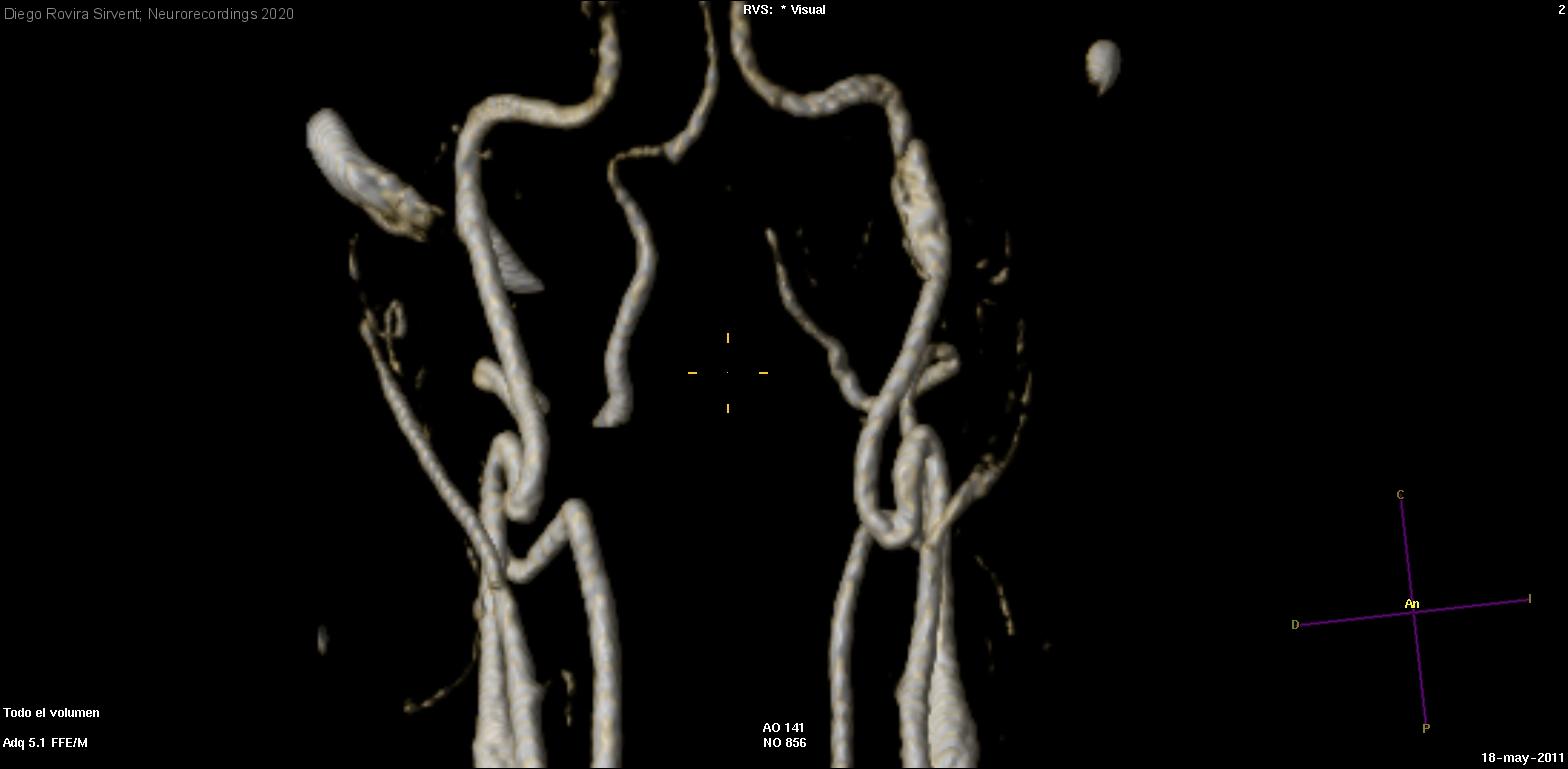

Diagnóstico final: Disección espontánea de arteria carótida interna izquierda con dilatación pseudoaneurismática. Parálisis XII par craneal izquierdo secundaria.

Varón de 33 años que consulta por desviación lingual con antecedentes de parálisis facial periférica izquierda hace unos 14 años, recuperada.Trabaja como transportista de muebles, actualmente en paro. Realiza actividad física frecuente (entrena en un...